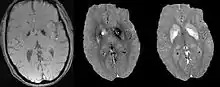

Differentiating calcification from iron

It has been confirmed in in vivo and phantom experiments that cortical bones, whose major composition is calcification, are diamagnetic compared to water.[11][18] Therefore, it is possible to use this diamagnetism to differentiate calcifications from iron deposits that usually demonstrate strong paramagnetism.[19] This may allow QSM to serve as a problem solving tool for the diagnosis of confounding hypointense findings on T2* weighted images.